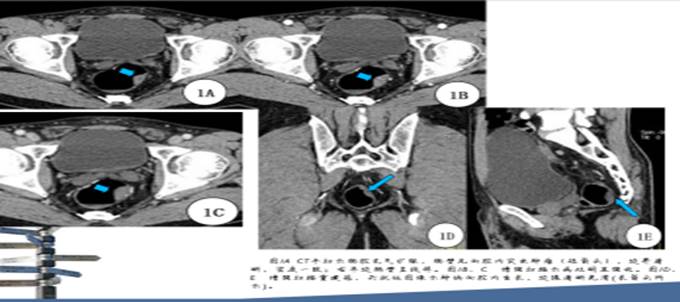

4.结直肠影像学表现;

5.结直肠癌TNM分期及诊断方法。